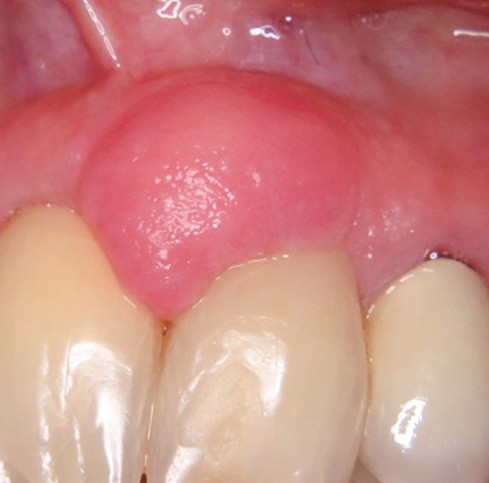

2. Épulis fibreux

- Nodule ferme, muqueuse de couleur normale (fig. 2a et b).